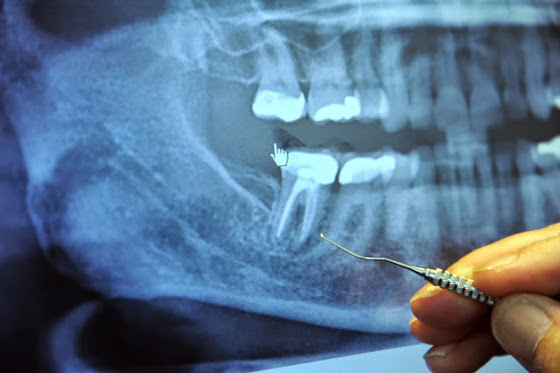

De aceea, oricât de bine ar fi obturaţi, în canaliculele dentinare ale dinţilor devitalizaţi rămân microbi în stare saprofită care devin virulenţi când rezistenţa organismului scade, favorizând astfel apariţia focarului de infecţie. De asemenea, microbii care pătrund pe la coletul dentar în canaliculele dentinare găsesc mediu de cultură (resturi de capilare rămase după îndepărtarea nervului şi arterei) şi migrează prin canalul radicular spre apex, la parodonţiul apical, producând fenomene inflamatorii cronice cu pierderi masive de ţesut osos.

Canalele radiculare curățate (de nerv, dar și de arteră) sunt în esență dinți morți care pot deveni incubatoare silențioase pentru bacterii anaerobe extrem de toxice, care pot în anumite condiții să-și croiască drum în sânge pentru a provoca o serie de probleme medicale grave, apărând la câțiva ani după lucrări pe canal dentar. Acești dinți nu dor (pentru că nu au nerv), arată bine, mulți ani nu dezvoltă pungi de puroi vizibile radiologic și deci este greu de urmărit rolul lor în cancer, boli de inimă sau reumatism.

Plombarea canalului radicular împiedică drenarea liberă a infecţiei, aceasta propagându-se din canalul radicular prin orificiul apical în spaţiul spongios al maxilarului, determinând infiltrat leucocitar la început, apoi distrucţia țesutului osos. Bacteriile ajunse în dentină nu se pot steriliza, rămân în stare latentă până găsesc o oportunitate de a se răspândi. Infecția se extinde la nivelul maxilarului producând necroză.

Actualmente se poate vorbi de o inconştiență a medicilor stomatologi, întrucât aceștia refuză de cele mai multe ori efectuarea extracţiilor dentare chiar și în ciuda insistențelor pacientului care este mai bine informat. Iar dacă aceasta se efectuează, nu practică chiuretaj alveolar şi nu recomandă administrarea antibioticelor cel puţin 7 zile (2 zile înainte şi 5 zile după extracţie). Orice dinte devitalizat cu obturaţie de canal oricât de corect ar fi realizată constituie un focar de infecţie, chiar şi dacă radiologic este în aparenţă normal.